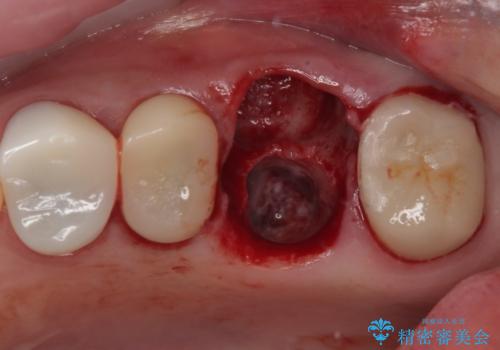

予後不良の奥歯 抜歯即時埋入インプラントによる補綴治療

- 奥歯のクラウンが土台ごと外れてしまったとのことで来院された患者様です。

保存可能ではありましたが、予後不良と患者様ご自身が判断されており、相談の結果抜歯即時埋入インプラントによる補綴治療を行うこととしました。

垂直方向への炎症が大きく、抜歯即時埋入はできたものの、即時荷重(インプラント埋入時の仮歯の装着)を可能とする安定値は得られませんでした。

それにもかかわらず、僅か4ヶ月で治療を終えることができ、以前の上顎洞底の挙上を行っていた頃よりも半年以上短縮することができました。